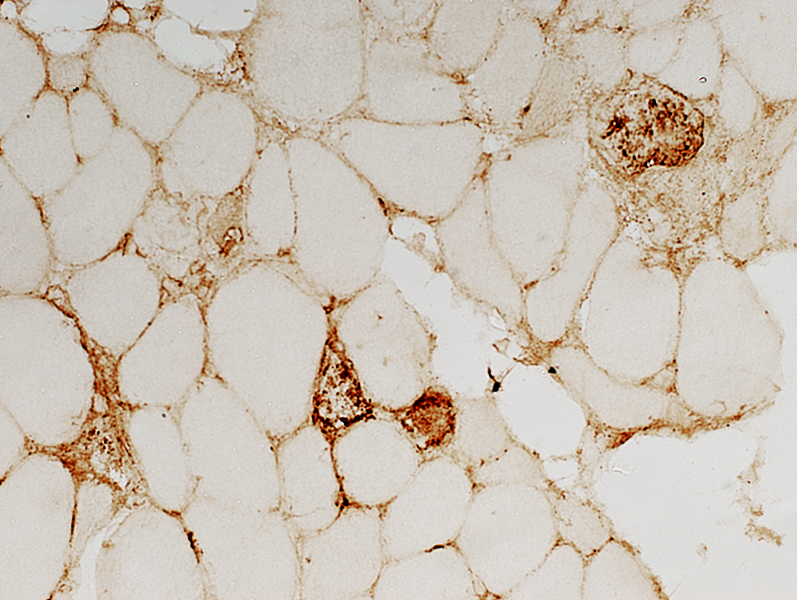

CD20 stain

CD20+ B-cells are a prominent component of some perivascular inflammatory foci.